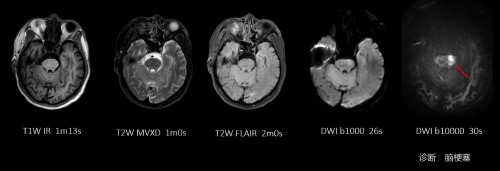

(3)脑梗塞检查:对于脑梗塞病灶的敏感性更强,可在发病数分钟至半小时内发现脑梗塞病灶。